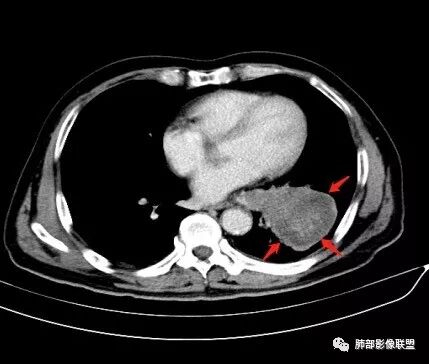

恶性没问题吧  ,哪位老师标示一下病灶

那些是淋巴结?哪是主病灶?

支气管如何?肺动脉?肺静脉?

尘缘:

淋巴结

采莲:

肺门是淋巴结肿大

尘缘:包绕支气管生长的肿瘤部分

采莲:支气管受压狭窄但没阻断

南边:我问一下:肺门支气管堵塞吗?

wonderful:

堵而不塞

尘缘:淋巴结外压支气管

南边:我发一个图

尘缘:至于到底长进去没有,层厚不够,不敢确定,个人认为没长进去。

马宁强:

南边:这些是淋巴结侵入支气管?

尘缘:@南边 不一定。

我觉得是外压为主。

远端还是通的。

有没有局部长进去,不好说。

金豆:

有点儿通而不畅感觉

南边:这病灶与支气管啥关系啊?

wonderful:压迫推移关系

是的,压迫推移

蔡磊:这算进入吗?

南边:与肺静脉啥关系?这样追下去是不是很恶啊

尘缘:@南边 肺静脉受侵

我觉得肉瘤样癌,混合癌可能比较大。

南边:病灶分为两大块,外围囊实性大肿块,支气管关系不密切,内带多发淋巴结,侵犯支气管、肺血管,恶性没问题,按理间叶为主,或不典型的癌,这不是一个中央型的肺癌,是外朝内进展的,奇怪的是边界这么清楚光滑,一般癌肉瘤、肉瘤类多,其次才是癌,远端也没有阻塞,大方向是这样,恶性,间叶来源?或者混合,恶性程度较高,鉴别就是结核,因为结核是妖